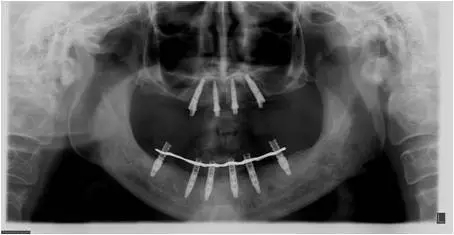

患者男性,51歲,全口無牙,下頜骨量尚可,上頜后牙區(qū)上頜竇底剩余骨高度嚴(yán)重不足,前牙區(qū)牙槽突較豐滿,主訴希望全口種植固定義齒修復(fù)。于2015年 9月接受種植治療:上頜采用All-on-4種植方案、下頜采用常規(guī)種植6顆種植體方案,種植后行即刻修復(fù)(圖1-2)。